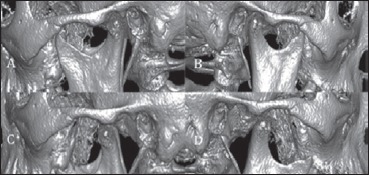

The condition is more common in women and in patients older than 50 years. Mixed, non-specific symptoms, the absence of a clear aetiological link and the scant knowledge about this clinical entity often delay diagnosis, as described by our experience. Physical examination and clinical history are useful diagnostic tools. An elongated styloid process may be palpated during intraoral examination and may provoke the pain. Correct indication to radiological investigation, dedicated technology and experience are needed in order to reach a diagnosis. Although plain skull radiographs might be sufficient to reveal the anatomical abnormality, CT of the head/neck and especially 3D-CT scan is considered as the gold standard for visualisation of the anatomically complex styloid process, as it avoids the problems of obscured overlapping anatomy. Moreover, it underlines the styloid process angulation, which is crucial for the surrounding anatomical relationships. Some controversy exists in the literature as to how many patients with an elongated styloid apophysis, at radiologic examination, do not exhibit any clinical symptoms. However, the surgical approach in patients with a diagnosis of Eagle’s syndrome is quite conclusive: surgical styloidectomy has, in fact, a cure rate of 80%.